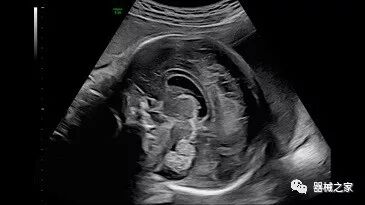

在RSNA 2018上发布的新成像被开发用于解决胎儿心脏和脑部成像问题。由于体积小且心率极快,因此难以进行详细的胎儿心脏评估。在18周时,胎儿的心脏大小与橄榄相当,每分钟跳动约150次。此外,结构本身非常复杂,婴儿不断运动,它始终是一个移动的目标。成像很重要,因为先天性心脏缺陷会影响全球每110个婴儿中的一个。

GE Healthcare用于胎儿超声的胎儿心脏和血管分析软件,在Voluson E10上提供,有助于在不到三分钟的时间内评估胎儿的心脏形状,大小和收缩性。称为辐射流的功能以三维视图显示血流。它还可以帮助显示缓慢流动的血液,例如神经血管循环。